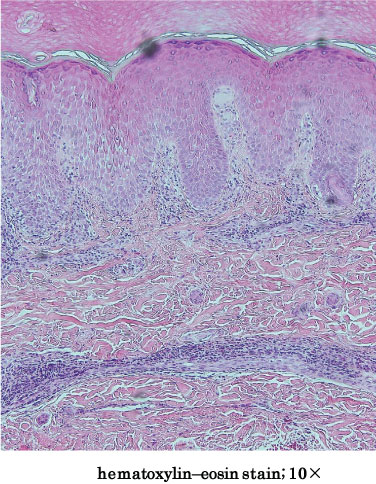

A 5-year-old healthy girl presented to our department with the complaint of moving subcutaneous linear red nodules on the plantar and dorsum of her foot (Figure 1A). She had visited Pattaya, Thailand, with her family 21 days ago and had walked barefoot on a beach. She did not exhibit any other symptoms, such as fever, abdominal pain, or respiratory abnormalities. Based on the information regarding the visit to Thailand and limited foot linear nodules, several parasites, including Ancylostoma ceylanicum, A. caninum, A. braziliense, A. duodenale, Uncinaria stenocephala, and Necator americanus, were suspected. Initially, the diagnosis was unclear; therefore, we obtained informed consent from her parents before surgery. Two days after her first visit to our department, the five suspected skin lesions were excised under general anesthesia. However, the moving nodules reappeared 9 days postoperatively (Figure 1B). Although we observed spongiosis with band-like eosinophil and neutrophil infiltration in the dermis, no parasite was identified from any of the excised specimens (Figure 2). She was orally administered ivermectin (3 mg) twice with at 1-week interval. Thereafter, the eruption did not reappear. We performed antibody screening using an antiparasite test (SRL Inc., Tokyo, Japan). Liver fluke and Cysticercus cellulosae showed false positive results; however, immunoglobulin G (IgG) antibody titer did not elevate in the recovery stage compared to that in the acute stage. Anti-IgG-specific antibodies were negative for Dirofilaria immitis, Toxocara canis, Ascaris suum, Anisakis, Gnathostoma, Strongyloides stercoralis, Paragonimus westermani, P. miyazaki, Fasciola hepatica, and Spirometra erinaceieuropaei at all stages. Based on these results, we suspected that the patient had acquired HrCLM because many cases of creeping disease caused due to hookworms have been reported in Thailand [4]. We discussed regarding the type of parasite that may have caused HrCLM and transition of Th2 cytokines in the current case. DNA was extracted from paraffin-embedded tissue at resection, and polymerase chain reaction (PCR) was performed using specific primers for A. ceylanium [4-6], A. caninum [4-6], A. Brasiliense [6,7], A. duodenale [4], U. stenocephala [6], and N. americanus [4]; however, no amplification was detected. For further investigation, the eosinophil count, IgE level, and serum immune-related Th2 cytokine levels (IL-3, IL-4, IL-5, IL-13, IL-18, and IL-33) were measured at the first visit, after 2 days postoperatively, at the time of recurrence (after 9 days), after the first dose of ivermectin (after 16 days), and after the second dose of ivermectin (after 42 days). The results of cytokine concentration are shown in (Figure 3). IL-3, IL-4, and IL-33 levels were below the detection limit. IL-13 and IL-18 levels were decreased postoperatively, elevated at recurrence, and decreased again after ivermectin administration. IL-5 levels gradually decreased.

Figure 2: The hematoxylin and eosin (H&E) section of the excised specimen shows spongiosis with band-like eosinophil and neutrophil infiltration in the dermis. View Figure 2